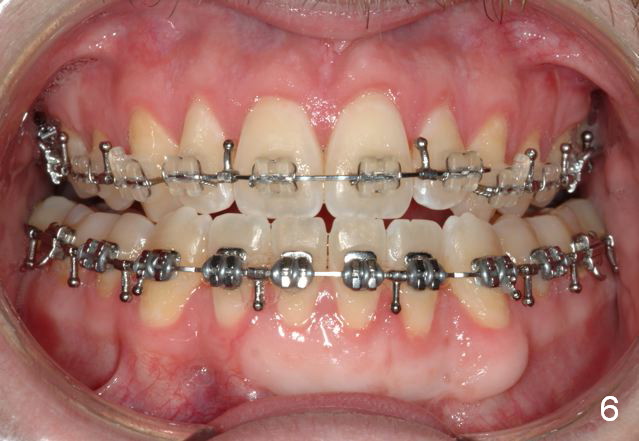

Initial bonding on 08/04/2014 (Fig.1-3); follow up appointments (09/20/2014 (Fig.4,5); 11/11/2014 (Fig.6,7), prepared for maxillary segmental surgery to expand, advance, and level.